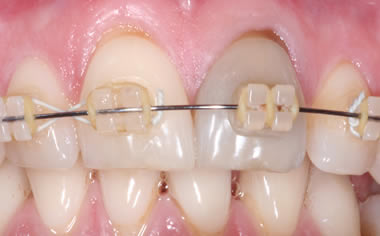

More front teeth replaced by dental implants

Case Three (4 images)